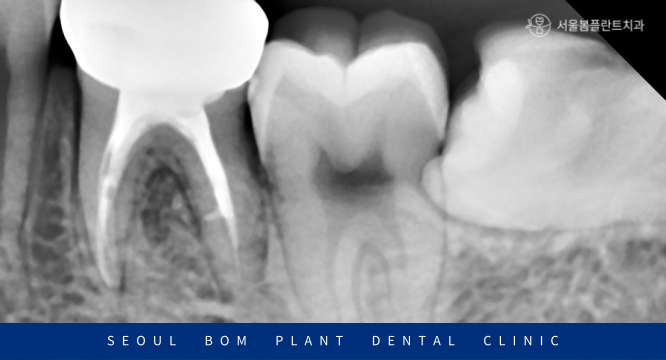

촬영 날짜 : 2022.11.30

정밀 검사를 위해

파노라마 사진과

작은 사진을 촬영하여

확인해 보았더니

아래턱 왼쪽 첫 번째 큰 어금니(#36)의

치근 분기부에서

까맣게 심한 골소실이 보였습니다.

신경치료를 마무리한 치아를 보면

이렇게 신경관 안이 하얗게

치과재료로 메워져 있는 것을

확인할 수 있습니다.